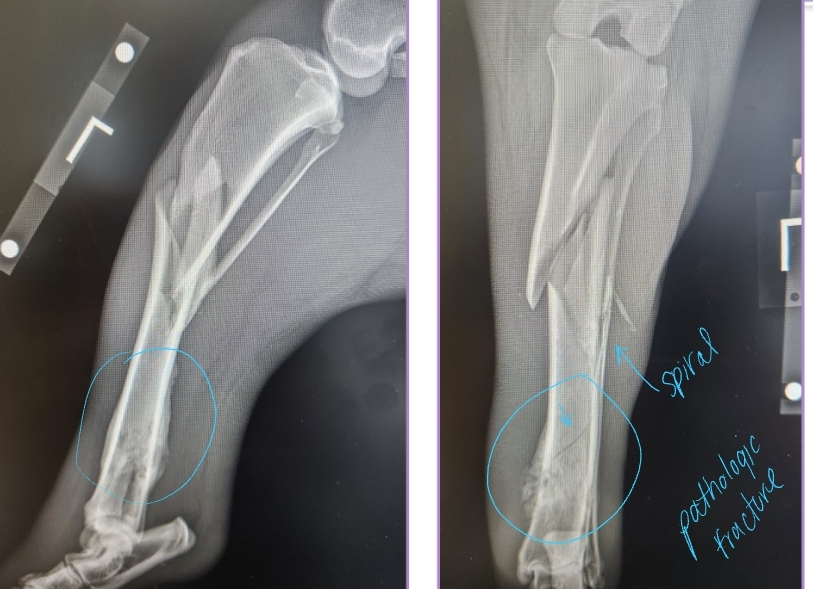

Primary Bone Neoplasia

Et: Osteosarcoma, Chondrosarcoma

Cs: Lameness, Muscle atrophy, Bone swelling

Dt: Radiographs #1, CT, Bone biopsy

Osteolysis, Osteoproliferation, Soft tissue swelling

“Away from the elbow, toward the knee”

proximal humerus, distal radius/ulna & distal femur, proximal tibia

Tx:

Amputation: Eliminates pain, MST 6 months

Amputation + Chemo: Eliminates pain, MST 12 months

Primary Stabilization + Chemo: Allows mobility, MST 12 months

Chemo adds extra time of survival!!